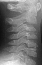

Patient is a 4 year old male who developed the insidious onset of neck pain and stiffness 4 days prior to admission. Over the intervening period, the patient suffered from worsening of his symptoms which led to increasing irritability and difficulty sleeping. On the day of admission, he was seen by a local pediatrician for severe neck pain. It was observed that his head was in a fixed position just slightly right of midline. The patient's past medical history was remarkable for two recent self-limited episodes of hives and urticaria on his trunk and extremities that was treated with prednisone. There was vague history of remote trauma about one month previously when the patient had been "horsing" around with his brother. The child had no evidence of a viral prodrome, constitutional symptoms or travel history. He was sent to a local hospital where radiographs of the cervical spine demonstrated calcifications in the C3-4 and C5-6 intervertebral disc spaces . Neurological exam was normal. The child's pain was refractory to morphine treatment and he was transferred to A.I. for the management of his intractable pain. On arrival, his physical exam was unchanged. Blood work revealed a WBC count of 12.7K with 75% PMNs and an ESR of 80. Radiographs of spine showed the presence of an addition calcification in his thoracic spine . He was treated with oral valium and a soft cervical collar. Over the ensuing 24 hrs the child demonstrated marked improvement of his symptoms and was switched to motrin. He was subsequently discharged.

The number of calcified discs varied from 1 to 12 (mean 1.69) . Symptomatic calcified discs are most common at C6-7. Radiologic examination shows images of calcium density in the normally radiolucent intervertebral discs. Anterior or posterior protrusion can be observed. The lesions demonstrate high density on CT and low signal intensity on MRI.